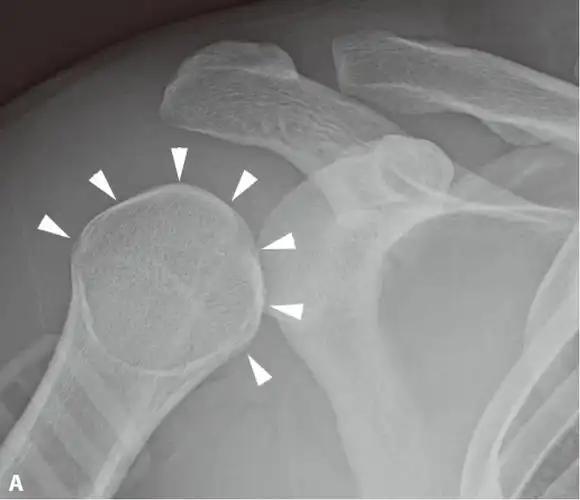

灯泡征高度提示肩关节后脱位

肩关节ap位x线平片显示肱骨头(白箭头)内旋导致的形态变圆("灯泡征").